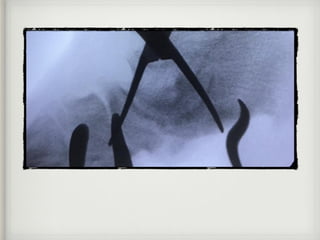

• Tratamientos quirurgicos basicos

Tratamientos

avanzados